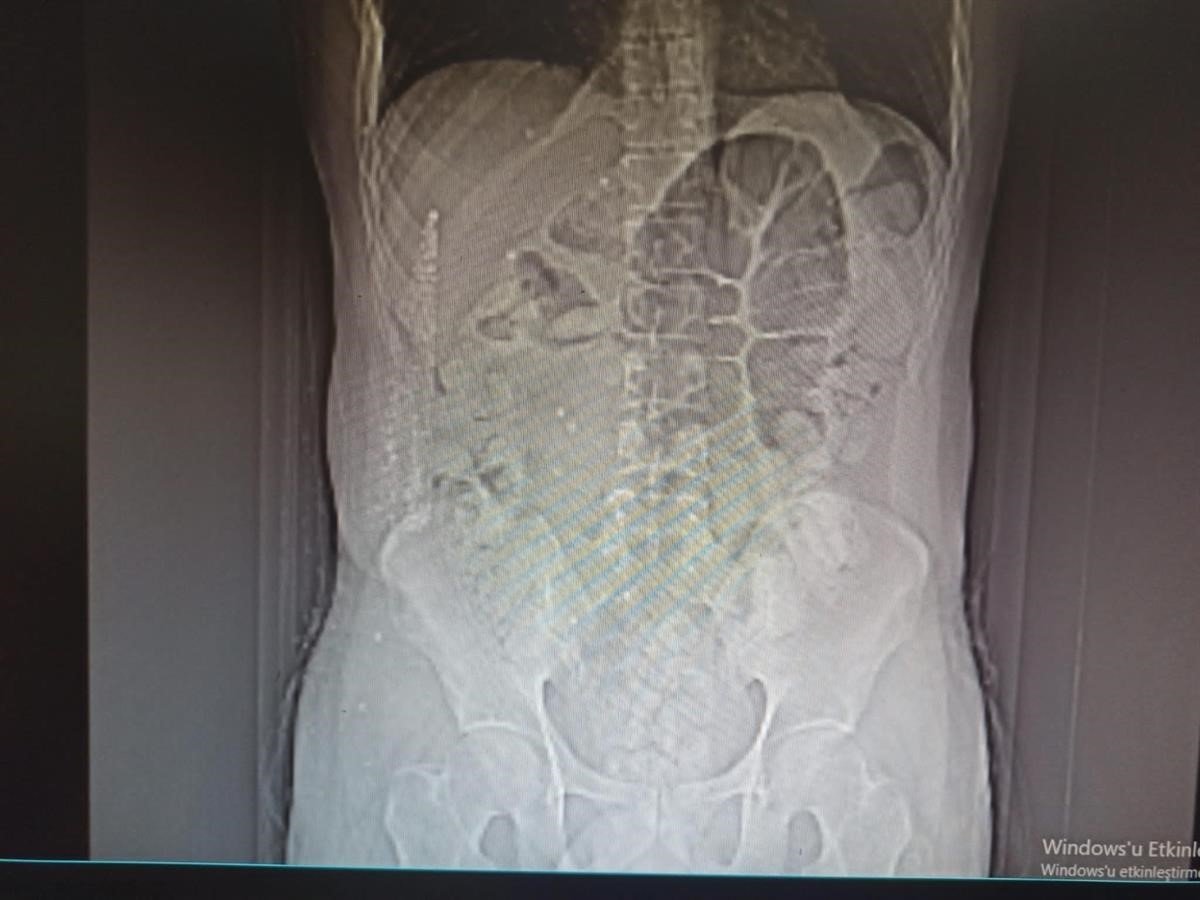

İl Emniyet Müdürlüğü Narkotik Suçlarla Mücadele Şube Müdürlüğü ile Kaçakçılık ve Organize Suçlarla Mücadele Şube Müdürlüğü ekiplerince yapılan ortak çalışmada; uygulama noktasında durdurulan, İran otobüsünde yolcu olarak bulunan İran uyruklu şüpheli M.K. (31) isimli kişiye yapılan tomografi çekiminde mide ve bağırsak kısmında uyuşturucu olabileceğini değerlendirilen çok sayıda yabancı cismin olduğu tespit edildi.

Yapılan tetkikler neticesinde M.K.'nın midesinden 64 parça halinde 711,86 gr gelen Afyon Sakızı ele geçirildi.